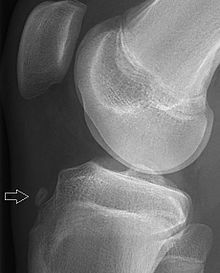

What is a Fabella?

A sesamoid bone located in the lateral head of the gastrocnemius muscle, behind the lateral femoral condyle.